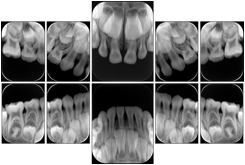

3. A dental provider wishes to capture a series of DICOM IO images for the patient’s dentition. The tooth morphology, teeth are divided into molars, premolars, canines and incisors, and a number of images for each jaw. The anatomic information was captured utilizing the triplet of schema. This standard code sequence is based on ISO 3950-2010, Dentistry - Designation system for teeth and areas of the oral cavity.

Every IO image should have anatomic information either through the primary or modifier sequence.

In most standard cases, images are oriented in structured layouts. These structured displays are useful to be shared between providers for reference purposes.

Table OO.1.1-1 shows structured display standard templates, where Viewset ID is based on the Japanese Society for Oral and Maxillofacial Radiology (JSOMR) classification provided by JIRA (Japan Medical Imaging and Radiological Systems Industries Association, www.jira-net.or.jp). Expected or typical teeth to be imaged location, region and designation codes are based on ISO 3950-2010, Dentistry - Designation system for teeth and areas of the oral cavity. For all the hanging protocols listed in OO.1.1-1, the value to use for Hanging Protocol Creator (0072,0008) is "JSOMR" and the value to use for Hanging Protocol Name (0072,0002) does not include "JSOMR" (e.g., "DL-S001A", not "JSOMR DL-S001A").